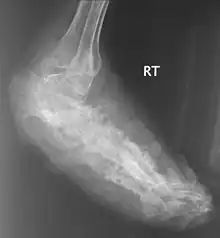

![]() | |

An infected foot | |

X rays and ultrasonography may be carried out to assess the extent of the disease. X rays findings are extremely variable. The disease is most often observed at an advanced stage that exhibits extensive destruction of all bones of the foot. Rarely, a single lesion may be seen in the tibia where the picture is identical with chronic osteomyelitis. Cytology of fine needle aspirate or pus from the lesion, and tissue biopsy may be undertaken sometimes.[11] Some publications have claimed a "dot in a circle sign" as a characteristic MRI feature for this condition (this feature has also been described on ultrasound).[14]